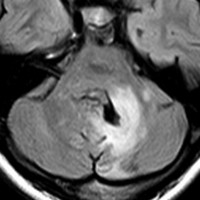

思春期の女の子にできた小脳腫瘍です。とても大きく見えますがほとんどが水たまり(のう胞といいます)。第4脳室が腫瘍で圧迫されて閉塞性水頭症になりました。のう胞の中に出血がありますが毛様細胞性星細胞腫では腫瘍内出血をしばしば見ます。右の写真で脳室が大きくなっています。こんなに大きいのに小脳症状は全くなくて,頭痛と嘔吐が症状でした。

赤で塗ったところだけが毛様細胞性星細胞腫です。これを取れば治ります。簡単な手術ですし後遺症も残りません。

手術後のMRIです。水頭症も改善してますから症状も消失しましたし,すぐに退院です o(^o^)o